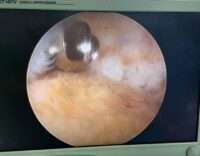

الدكتور نوار الفتلاوي قال” تمت ازالة النتوء العظمي و الالتهاب المحيط به كلياً عن طريق الناظور و من خلال فتحات جراحية صغيرة جداً دون اللجوء الى الجراحة التقليدية لازالته وفي وقت قياسي دام ساعة ونصف فقط .